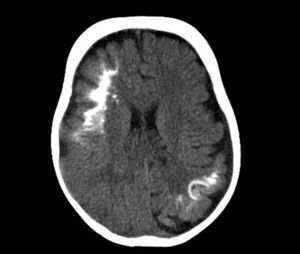

Tomografía axial computarizadaLa tomografía cerebral es una técnica que se utiliza frecuentemente en urgencias, para la valoración de un niño que comienza con hemiparesia o convulsiones. Los hallazgos característicos son la presencia de pérdida de volumen parenquimatoso, agrandamiento del ventrículo y el agrandamiento del plexo coroideo. A partir del año de edad la tomografía axial computarizada puede detectar calcificaciones (fig. 6), que normalmente no serían visibles en una radiografía simple, y es más sensible en la detección de calcificaciones que la RM14,37.